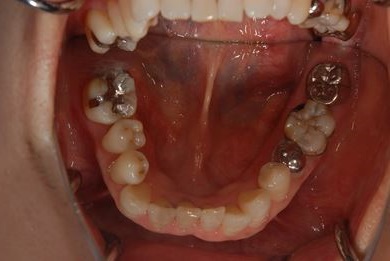

インプラント治療+セラミック治療

| カテゴリー | 【インプラント治療】【セラミック治療】 | ||||||||||||||||||||||||||||||||

| 性別/年齢 | 女性 / 61歳 | ||||||||||||||||||||||||||||||||

| 主訴 | 奥歯がぐらつく。 | ||||||||||||||||||||||||||||||||

| 治療方針 | インプラント治療にて機能的・審美的回復を行う。 | ||||||||||||||||||||||||||||||||

| 治療内容 | インプラント1本、メタルボンドセラミッククラウン3本(メタルボンドセラミック用土台2本) | ||||||||||||||||||||||||||||||||

| 総治療費 | 625,538円 | ||||||||||||||||||||||||||||||||

| 治療期間 | 1年0ヶ月 |